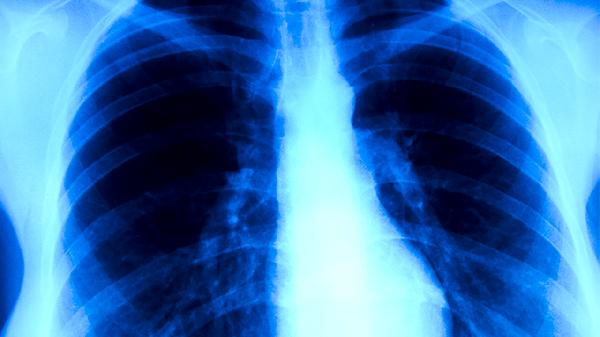

胸部X線能顯示肺部特征性改變?nèi)鐫B出性病灶、纖維鈣化灶或空洞形成。早期肺結(jié)核可能僅表現(xiàn)為肺尖部小片狀陰影,隨著病情進(jìn)展可出現(xiàn)典型的上葉尖后段或下葉背段病變。該檢查對(duì)發(fā)現(xiàn)無(wú)癥狀感染者具有重要價(jià)值,但需注意與肺炎、肺癌等疾病進(jìn)行鑒別。